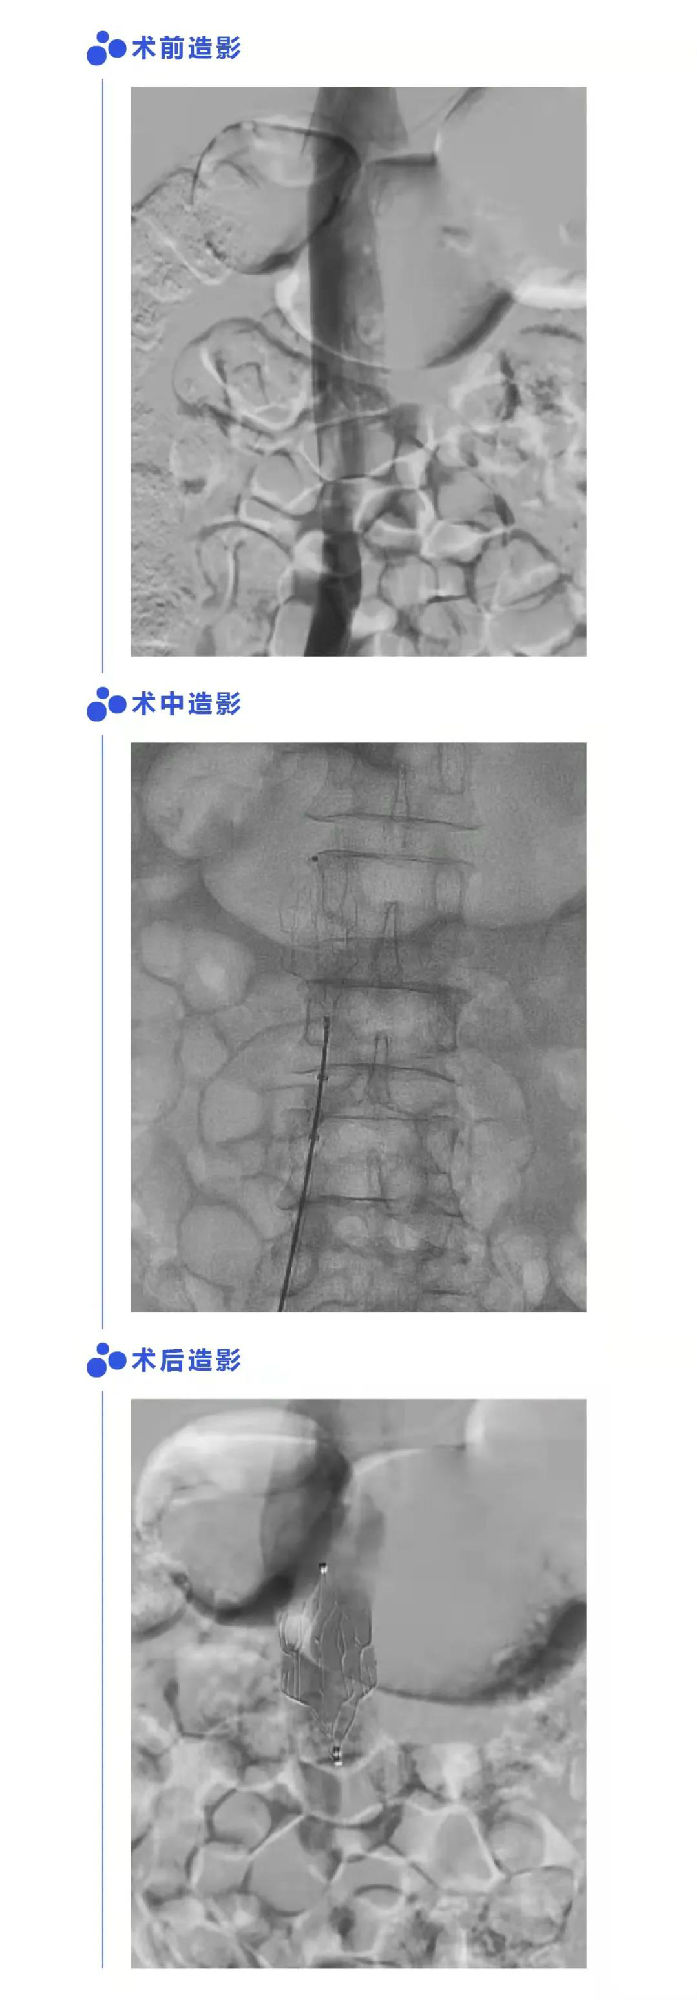

患者男,57岁,因外伤至左髌骨骨折,术前超声提示左侧腘静脉有血栓形成。经评估符合手术指征,植入Fitaya™腔静脉滤器,滤器定位准确,形态好;经血栓清除和抗凝治疗后血栓消失,置入术后56天顺利取出滤器,无移位、倾斜。取出术后24天随访,超声提示下腔静脉通畅,原滤器置入部位无血栓形成。